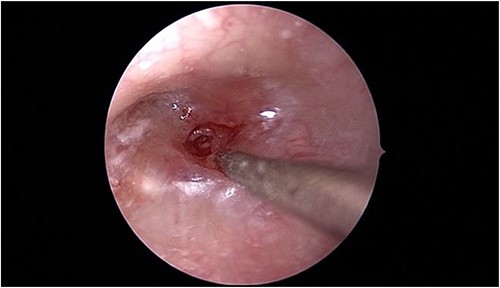

In view of the findings, the patient was taken to the operating room for left tympanomastoidectomy with bilateral tympanostomy tubes insertion and intraoral drainage of the left BA. Intraoperatively, the left tympanic membrane was already healed; however, it was significantly thickened and inflamed during myringotomy. The middle ear space was full of granulation tissue with no purulent discharge that could be retrieved (Fig. 3).

Intraoperative endoscopic view of the left middle ear cavity filled with granulation tissue.